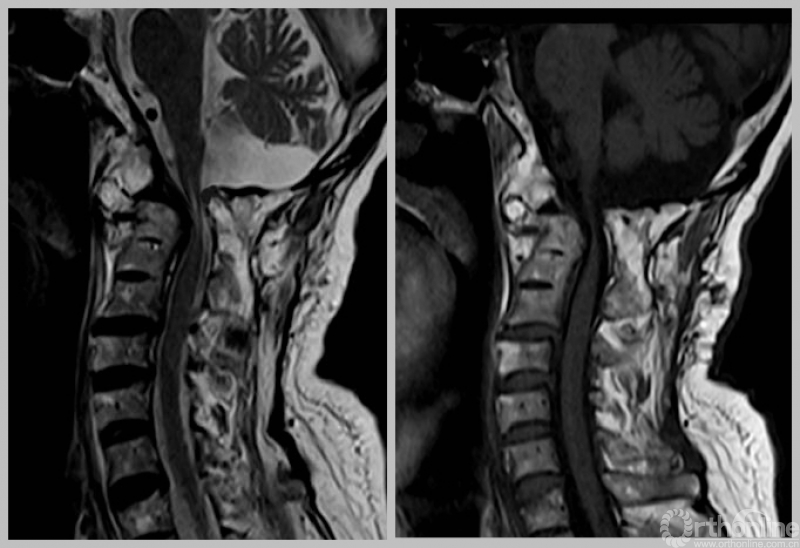

MRI

术后MRI(患者术后四肢麻木、乏力,发音、吞咽困难改善。)